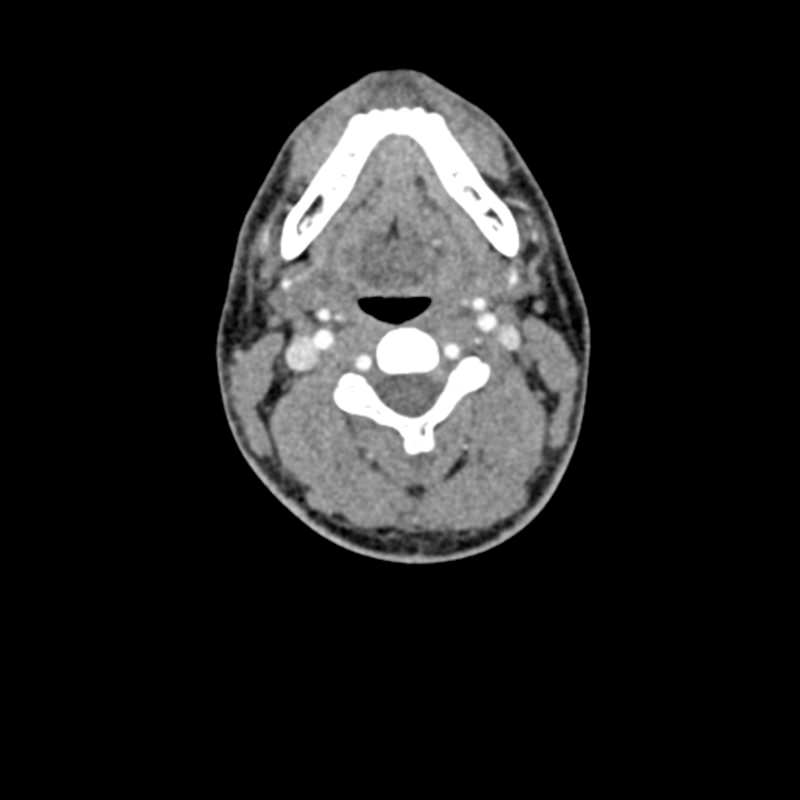

Dieses Phantom ist aus echten Patientendaten erstellt und wird mit neuester Technologie hergestellt. Knochen, Gefäße und Weichteilgewebe werden authentisch dargestellt mit realistischen CT-Werten für alle Gewebe bei 120 kVp Röhrenspannung in der CT. Wenn das Phantom vorwiegend bei anderen Röhrenspannungen (z. B. 100 kVp) eingesetzt werden soll, kann die Kalibrierung der CTWerte auf Wunsch entsprechend angepasst werden. Das Phantom liefert realistische Gewebekontraste in der Röntgen-Bildgebung. Lufträume sind durch ein Material mit etwa -80 Hounsfieldeinheiten aufgefüllt.

Das Kopf - Phantom liefert eine äußerst realistische Simulation einer Kopf- und Hals-CT-Angiographie (mit arterieller Kontrastierung) eines Patienten mit einer arteriovenösen Malformation auf der rechten Seite. Das Phantom wird in originalgetreuem Maßstab geliefert und beinhaltet die Halswirbelsäule bis zur Grundplatte des fünften Halswirbels.